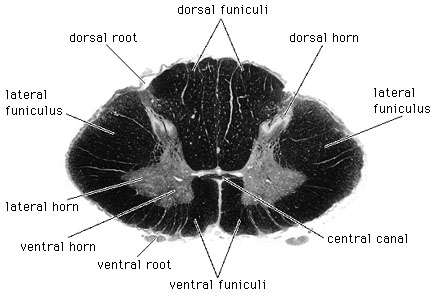

4. Composed of gray & white matter – histologically H shaped grey matter surrounded by white matter

a. Gray matter - unmyelinated tissue, mainly cell bodies, soma, nissl bodies

b. White matter - myelinated tissue, mainly axons

1. Central canal - contains cerebrospinal fluid – internal canal

4. Anterior median fissure – deep groove along the ventral surface

5. posterior median sulcus – shallow groove on the dorsal surface

6. dorsal roots – sensory, afferent fibers, dorsal root ganglion, structurally unipolar, neurons from the periphery

7. ventral roots- motor, efferent fibers, dendrites and cell bodies in ventral horns, structurally - multipolar

1. Gray matter

a. Composed of neuron cell bodies,shaped like an H or butterfly

b. Six projections called horns:

1. Two dorsal gray horns

2. Two ventral gray horns

3. Two lateral gray horns - found in thoracic lumbar

c. Transverse bar called the gray commissure

d. Central canal in center of gray commissures

2. White matter

1. Anterior median fissure

2. Posterior median sulcus

b. contains six fasciculi

1. Two posterior

2. Two lateral

3. Two anterior